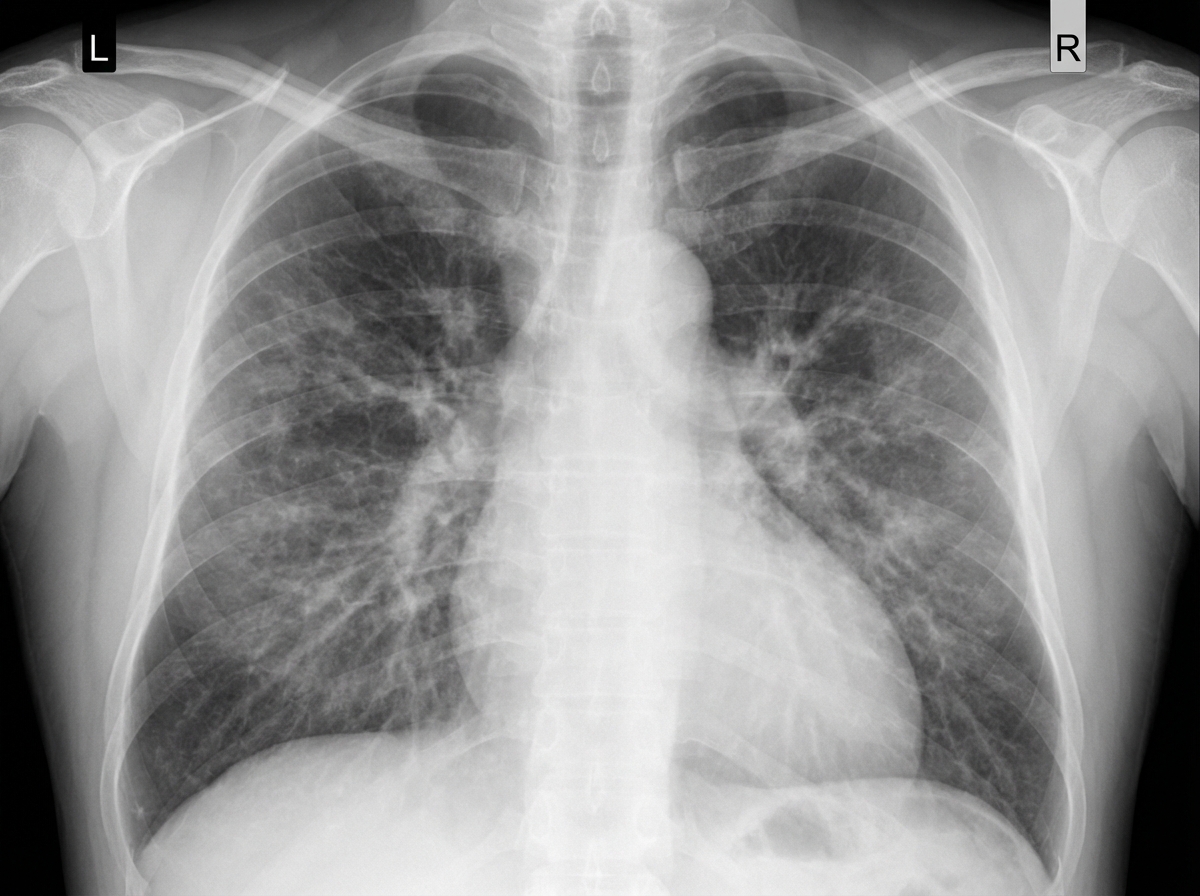

A 68-year-old man presents with shortness of breath, particularly when walking up stairs and when lying down to go to sleep at night. He also complains of a chronic cough and states that he now uses 2 extra pillows at night. The patient has a history of type 2 diabetes that is well-managed with metformin. He also takes Prozac for a long-standing history of depression. The patient has a 60-pack-year smoking history. He also has a history significant for alcohol abuse, but he quit cold turkey 15 years ago when his brother was killed in a drunk driving accident. Both he and his brother were adopted, and he does not know other members of his biological family. Despite repeated efforts of patient counseling, the patient is not interested in quitting smoking. The physical exam is significant for an obese male using accessory muscles of respiration. The vital signs include: temperature 36.8°C (98.2°F), heart rate 95/min, respiratory rate 16/min, and blood pressure 130/85 mm Hg. The oxygen saturation is 90% on room air. Additional physical exam findings include cyanotic lips, peripheral edema, hepatomegaly, and ascites. The cardiovascular exam is significant for an S3 heart sound and elevated JVP. The pulmonary exam is significant for expiratory wheezing, diffuse rhonchi, and hyperresonance on percussion. The laboratory test results are as follows: BUN 15 mg/dL pCO2 60 mm Hg Bicarbonate (HCO3) 32 mmol/L Creatinine 0.8 mg/dL Glucose 95 mg/dL Serum chloride 103 mmol/L Serum potassium 3.9 mEq/L Serum sodium 140 mEq/L Total calcium 2.3 mmol/L Hemoglobin 26 g/dL Bilirubin total 0.9 mg/dL Bilirubin indirect 0.4 mg/dL Iron 100 Ferritin 70 TIBC 300 The posterior-anterior chest X-ray is shown in the image. Which of the following interventions is indicated for decreasing the mortality of this patient?